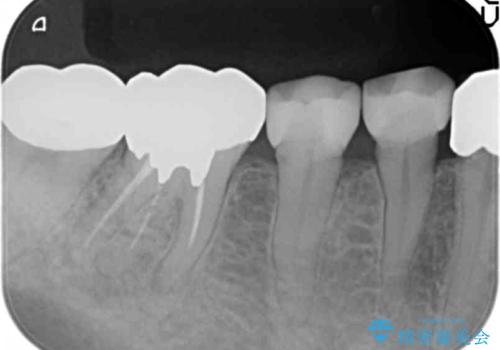

精査したところ、被せ物を入れたばかりの右下の小臼歯(右下5)は不可逆性歯髄炎により神経をとる処置(抜髄)が必要な状態でした。

根管治療後、セラミッククラウンによる補綴治療を行いました。